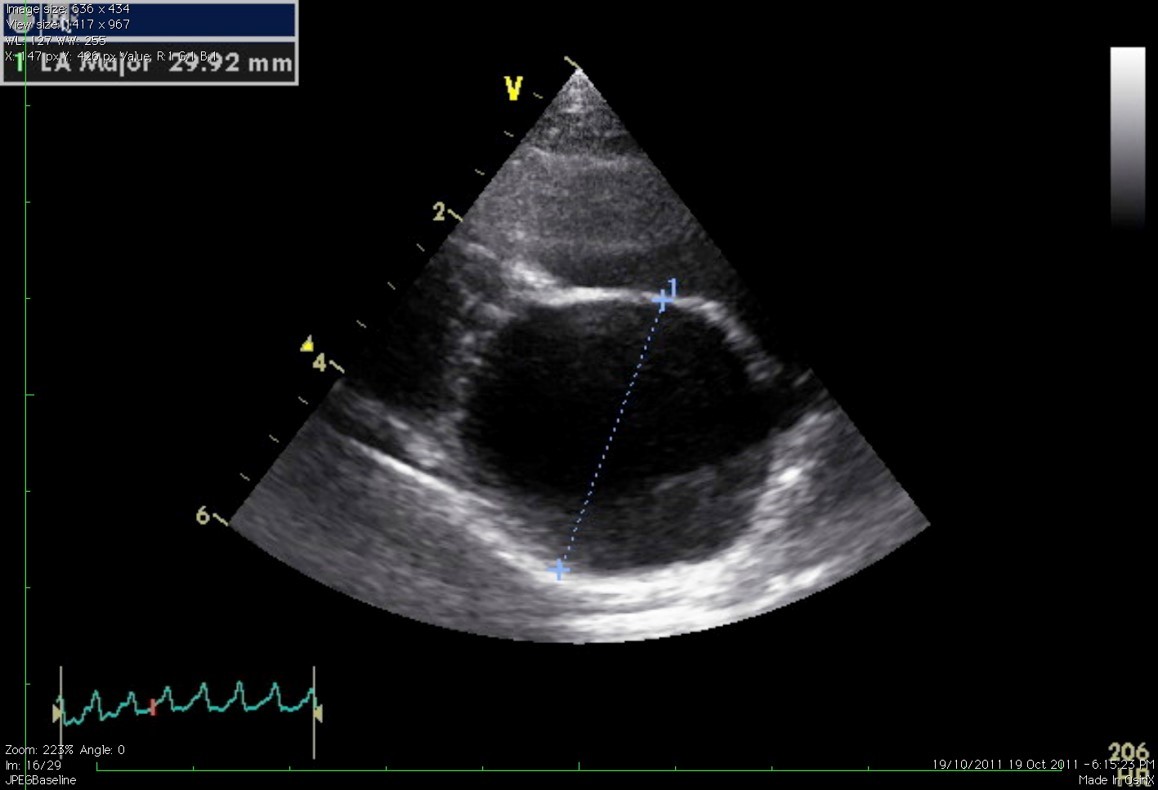

What does this show?

LA size